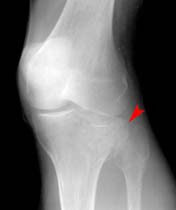

When will i be able to walk without crutches and when will i be able to walk without a limp. After tibial plateau fracture surgery you will experience pain, swelling, stiffness and decreased range of movement in your knee. A fracture is another word for a break. There is normally a recent history of trauma to the knee. People should always follow their doctor's recommendations about returning to walking, exercising, and other physical activity after a leg fracture. Most importantly, by this stage you should not have any residual pain other than an ache and some stiffness when you wake. People are generally unable to walk. (obq09.166) a large posteromedial tibial plateau fracture pattern, as seen with the bicondylar tibial plateau fracture shown in figures a and b, is important to recognize because of which of the following factors? He didn't give me any other instructions other than i worked the next several weeks on my limp and stamina. Tibial plateau fracture with metal plate fixation. Tibial fractures are common and usually caused by an injury or repetitive strain on the bone. Tibial plateau fractures occur just below the knee joint and can involve the cartilage surface of the knee. At this stage, after eight weeks of rehab exercise, it's worth trying to determine what someone with a tibial plateau fracture should be able to do and should not attempt to do. Avulsion fracture of margin of lateral tibial plateau just below joint line. Proper identification and management of these injuries will help to restore limb function. Active flexion and passive extension are encouraged for 6 weeks, after which period active. Pcl and lcl associated with medial plateau fracture.